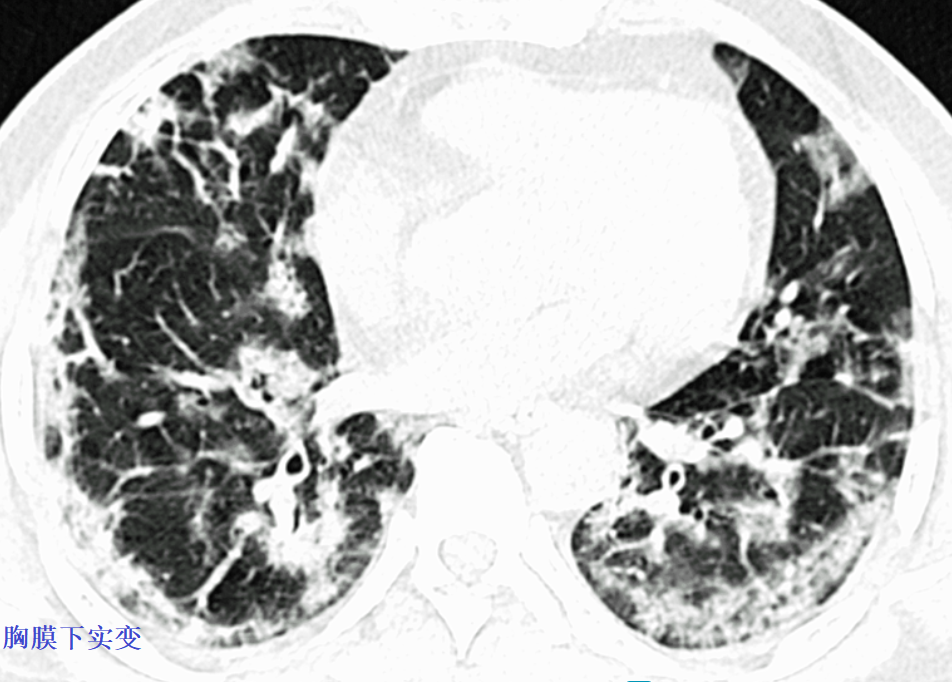

例1,磨玻璃+实变+胸膜下分布为主,典型的新冠肺炎。

例2,磨玻璃内见网格状阴影,胸膜下分布为主,典型的新冠肺炎。

例4,磨玻璃,胸膜下分布为主,铺路石征,也是新冠肺炎的表现。

例5,新冠肺炎CT,虽然看着四不像,但是胸膜下分布为主。